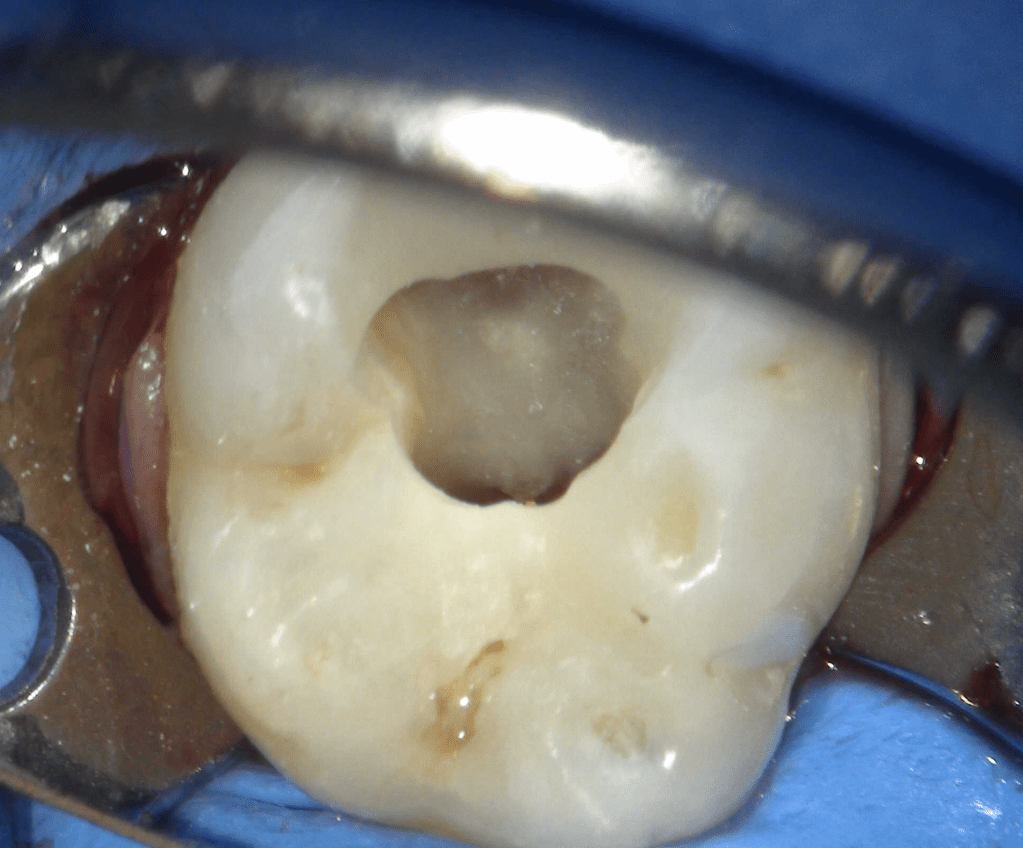

Reconstrucción preendodóntica

Reco preendo + 4 conductos molar superior